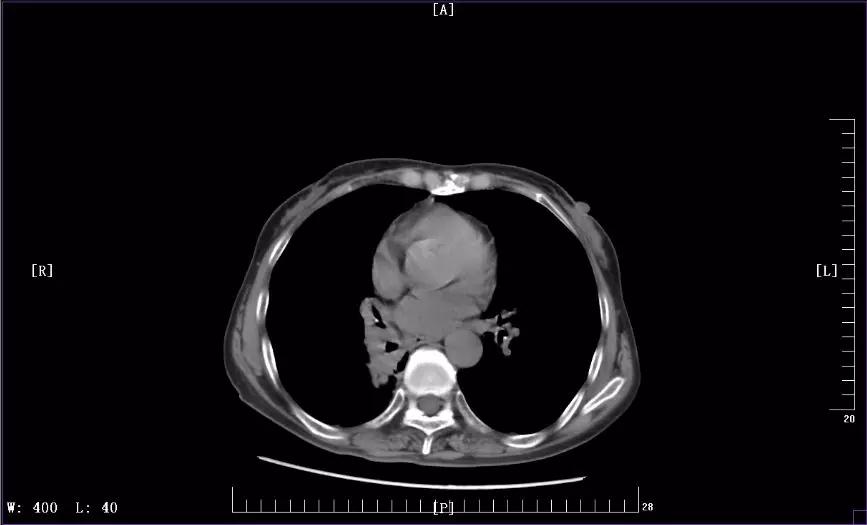

下圖是徐麗參加KEYNOTE-407臨床試驗(yàn)前后CT影像對(duì)比圖:

2018年12月最近一次治療后CT影像